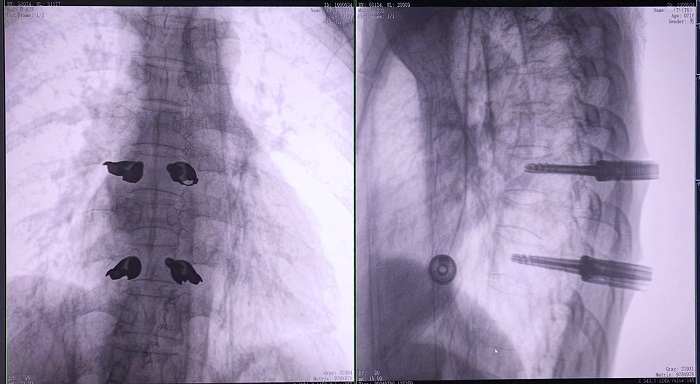

③机器人辅助胸椎手术操作难点之精准置钉

传统开放手术中,胸椎的手术视野相对受限,螺钉的置入主要依赖于医生的经验和手感,存在一定的主观性。

普爱医疗骨科手术机器人的高精度机械臂,按照规划好的路径及角度,自动精准定位穿刺点,医生打入克氏针后,正侧位图像显示精度满足预期,医生完成置钉等后续手术操作。